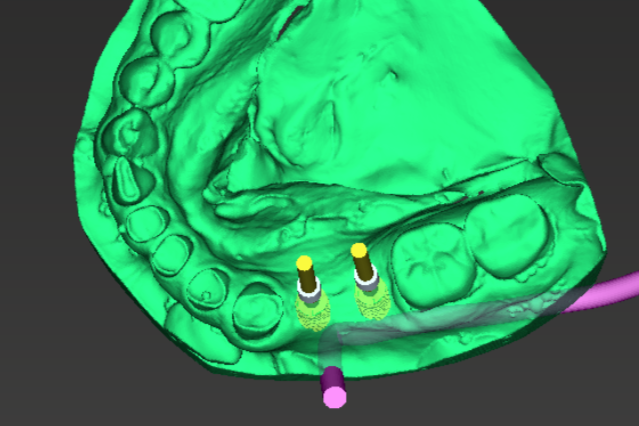

We offer state of the art 3-D x-ray imaging which allows a superior diagnostic level to 2-dimensional imaging. This imaging allows us to find pathology and plan implant cases with a level of precision beyond anything we could imagine 10 years ago.

Digital implant planning and the surgical guides they generate simplify the process

When a tooth is lost, an implant is essentially a fake tooth root. After the implant is placed and allowed to heal in, a tooth is attached. With 3-D x-ray and digital planning, the results can be excellent.